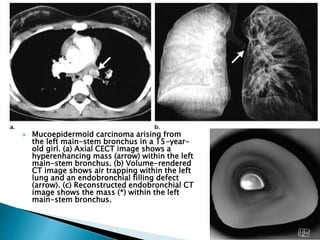

 Mucoepidermoid carcinoma arising from

the left main-stem bronchus in a 15-year-

old girl. (a) Axial CECT image shows a

hyperenhancing mass (arrow) within the left

main-stem bronchus. (b) Volume-rendered

CT image shows air trapping within the left

lung and an endobronchial filling defect

(arrow). (c) Reconstructed endobronchial CT

image shows the mass (*) within the left

main-stem bronchus.